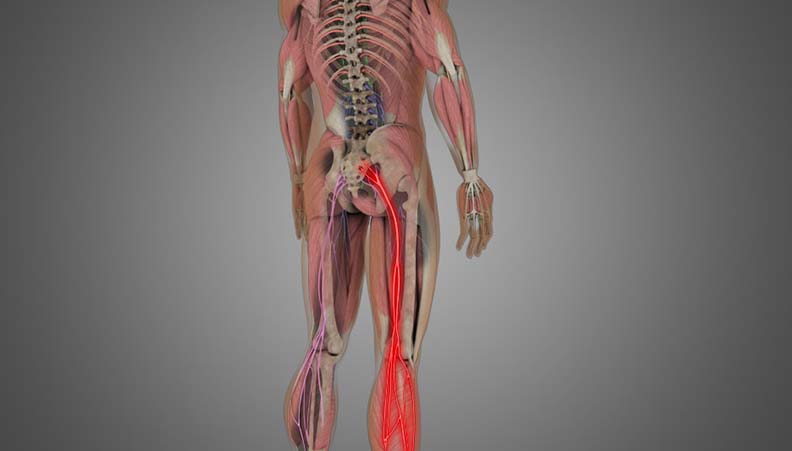

Sciatica is a common condition characterized by pain that radiates along the path of the sciatic nerve, which extends from the lower back through the hips and buttocks and down each leg. Typically, sciatica affects only one side of the body and is often associated with tingling, numbness, or muscle weakness in the affected leg. Understanding the causes, symptoms, and available treatments for sciatica is essential for managing this often-debilitating condition.

The primary symptom of sciatica is pain that radiates from the lower back to the buttock and down the back of the leg. Other symptoms may include: